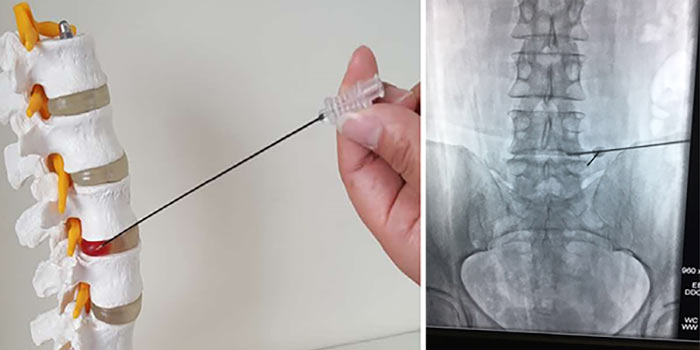

Диагноз подтверждают с помощью биопсии. Врач получает фрагмент опухолевой ткани и отправляет в лабораторию для цитологического, гистологического исследования, молекулярно-генетических анализов. Материал для биопсии может быть получен разными путями:

- Чаще всего проводят пункционную чрескожную биопсию с помощью иглы, которую вводят под контролем рентгена.

- Реже часть опухоли или всю ее целиком удаляют хирургически. Такая биопсия называется соответственно инцизионной и эксцизионной.

Для стабилизации позвонков и уменьшения болей может быть выполнено миниинвазивное вмешательство. В позвонок вставляют иглу и восполняют объем костной ткани специальным цементом.